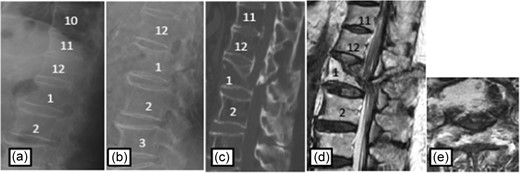

Case 1

Plain radiographs on initial assessment (a) and on admission (b); Sagittal CT image (c) showing the hyperextension fracture at T12; MRI T2-weighted image (d, e) showing the epidural hematoma compressing the dura matter.